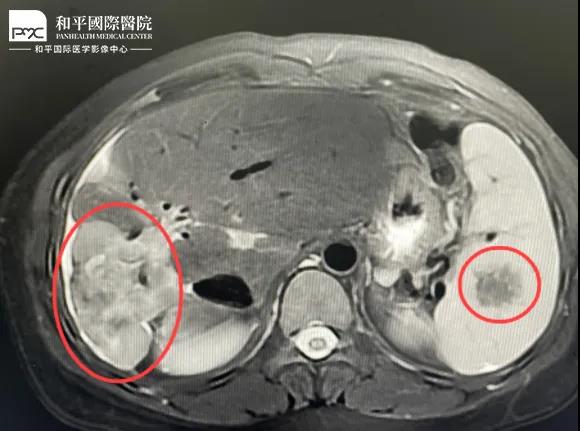

檢查結(jié)果對于這家人而言猶如晴天霹靂,經(jīng)核磁共振等相關(guān)檢查,當(dāng)?shù)蒯t(yī)生懷疑是肝癌,建議手術(shù)治療。悲痛中,家人們對這樣的結(jié)果表示無法接受,想要多去幾家醫(yī)院看看,為了進一步確診,王小姐來到我院醫(yī)學(xué)影像中心進行檢查,事情竟發(fā)生了戲劇性反轉(zhuǎn)。

根據(jù)影片分析,結(jié)合王小姐有系統(tǒng)性紅斑狼瘡的病史,長期服用激素,免疫力低下,近期又有低熱盜汗的癥狀,影像中心執(zhí)行主任侯文杰初步判斷王小姐是得了肝結(jié)核,并不是肝癌!

由于肝結(jié)核是臨床非常少見的病例,單靠影像診斷是很難診斷正確的,在侯主任的建議下,王小姐做了穿刺活檢,診斷結(jié)果的確是肝結(jié)核。